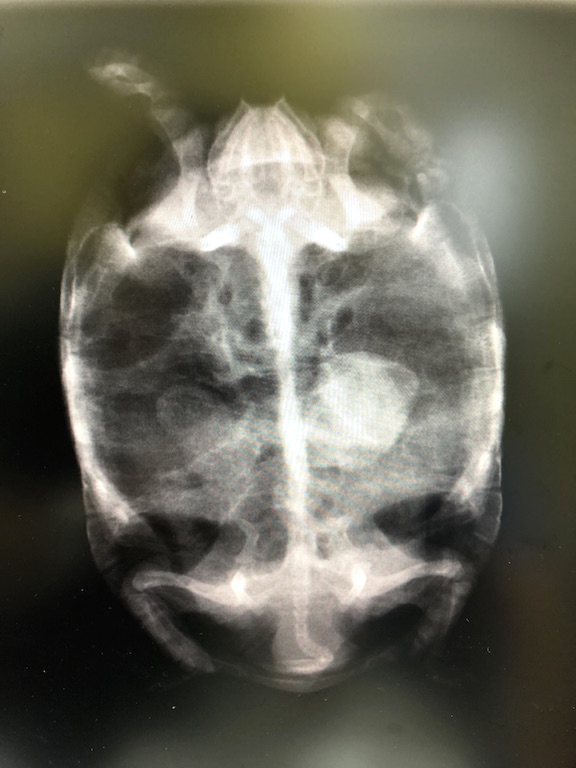

タイガーの結石を疑った私は、すぐに近所の動物病院でレントゲン撮影をして頂きました。

悪い予感は的中しました。胸のあたりに石らしき物体が写り込んでいます。

現在のタイガーは甲長10cm/体重220g、奇しくも当時の2号と同じサイズです。

状況を説明した後、詳細を把握するために再度レントゲンの撮影を行います。 横からの画像に驚きました。

ここまで大きな石を抱えていたとは・・・

位置やサイズを考慮すると骨盤付近まで下りてくることは期待できず、タイガーを救う手段は早急な開腹手術しかなさそうです。